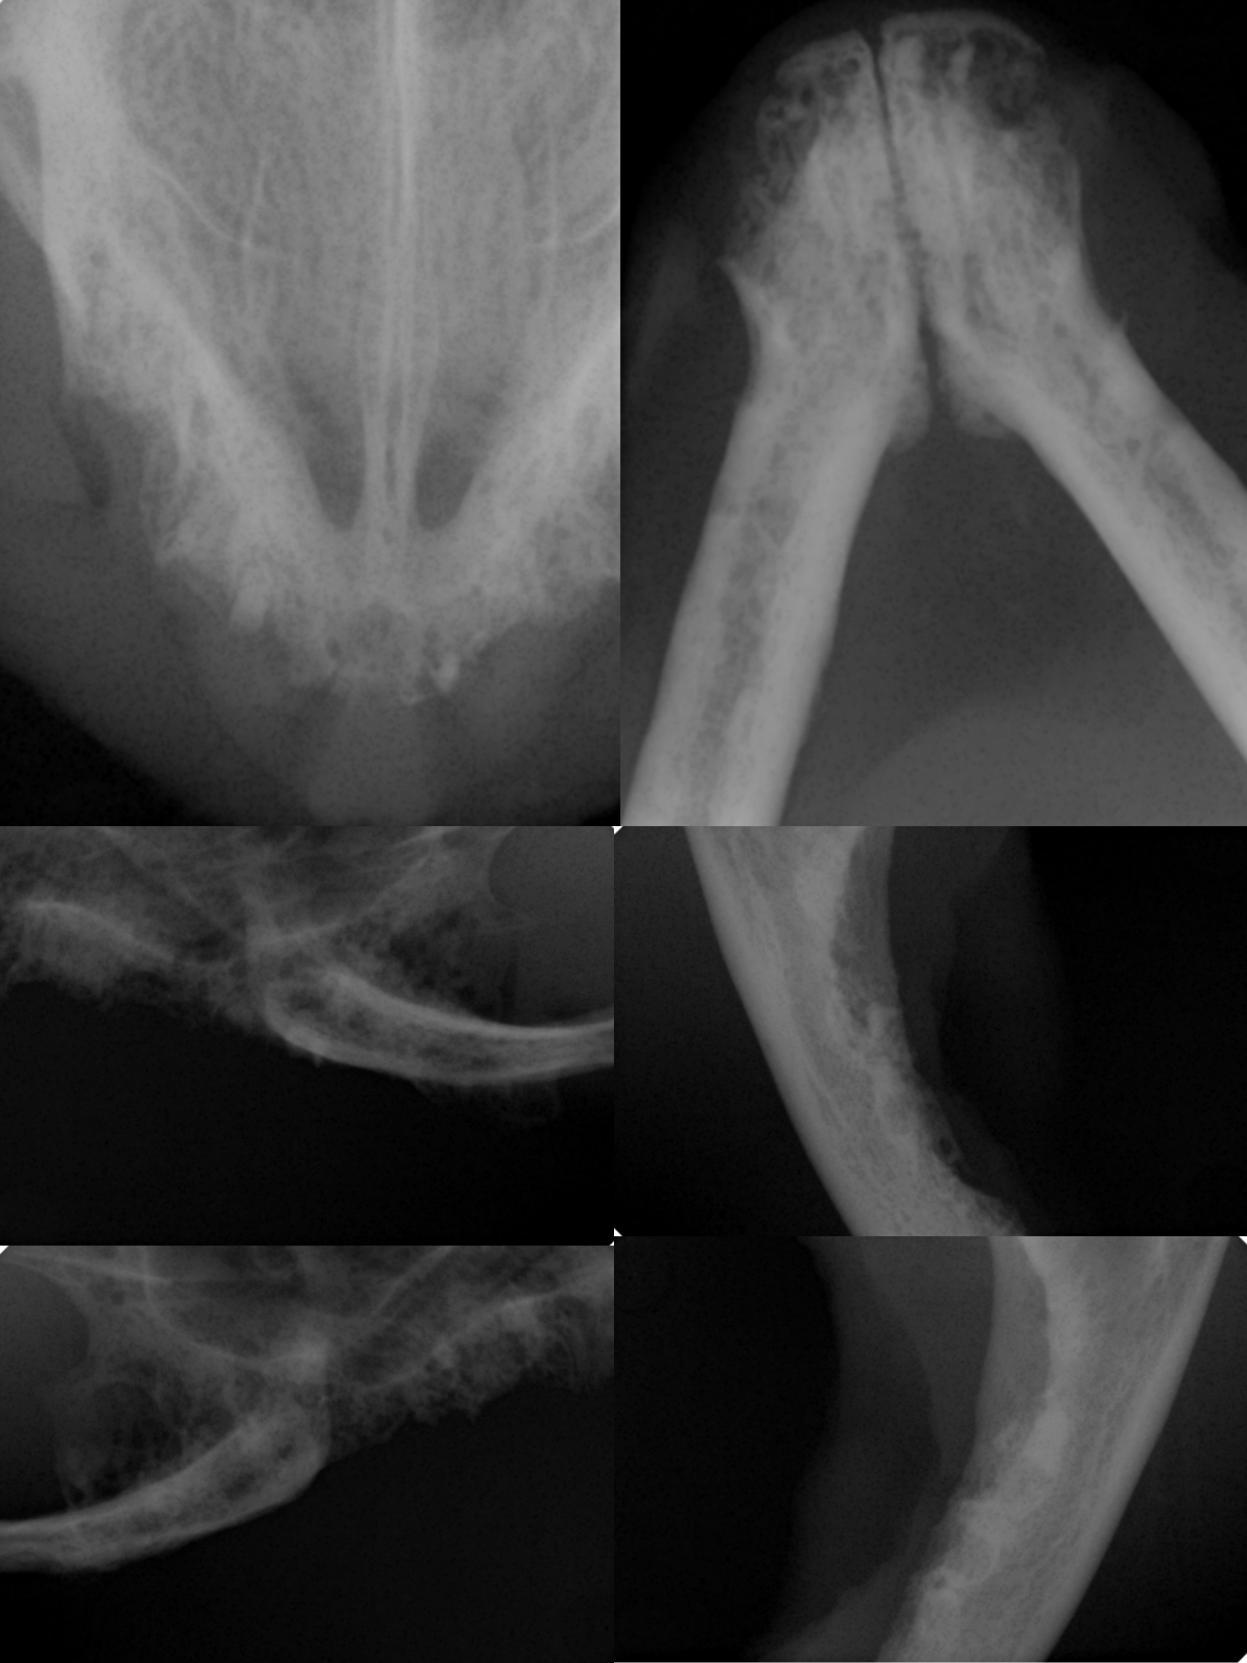

3// 影像学检查

可见牙根残留,提示反复性口炎的潜在性原因或许是全口拔牙未彻底。

前期因主人告知外院已确定全口拔牙,不存在残留牙根,所以我院选择激光理疗治疗。但炎性增生控制不乐观,影响生活质量,经商量决定配合激光灼烧治疗,麻醉后拍x光发现牙根残留,因此进行残留牙根拔除术并激光灼烧。